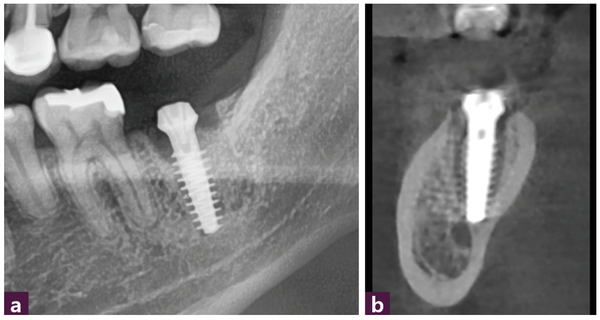

본 증례에서는 3mm 정도의 잔존골에 1~2mm의 식립구를 형성해 MagiCore의 마지막 나사산을 잔존골에 engage 시킬 수 있었다. 초기 식립 토크값(initial torque value)은 35Ncm이었다. 신경관 근처 부위의 식립구 형성과 식립 후 확인은 portable standard 촬영을 통해 확인했다. [그림 4]

식립 전 계획했던 대로 Magic Cuff 5mm와 Magic Fin Thread 부분의 13mm 길이를 더한 18mm를 이용해 3mm 가량의 잔존골에 1~2mm의 식립구를 형성한 후 MagiCore를 성공적으로 식립했다. [그림5]